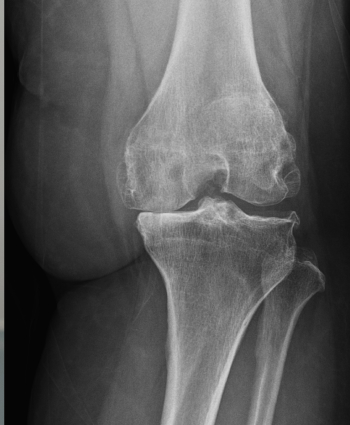

X-ray 관절 간격, 관절 정렬, 뼈 변화 확인